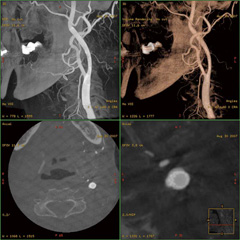

axial/coronal/sagittal/obliqueなどの断層像,MIP,VR,MPR,navigator画像などの再構成画像を同時に表示可能である。4分割画面において3D画像と3断面画像を同時に表示でき,かつ,すべての画像においてカーソルを連動させて動かすことができるため,より詳細な血管走行や構造の把握が可能となり,栄養血管の特定を容易に行うことができる(図4)。ワークステーションの操作性の良さがスムーズな診断を可能にする。

図4 Advantage Workstationにおける4分割画面例